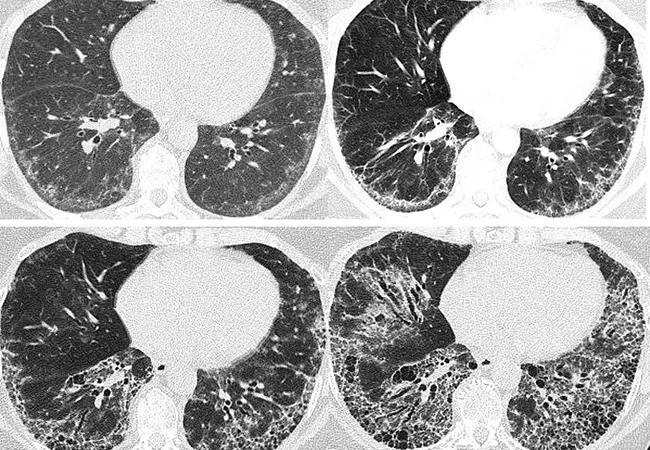

Above, serial chest scans of a 57-year-old female with systemic sclerosis over eight years demonstrate the progression of interstitial fibrosis.